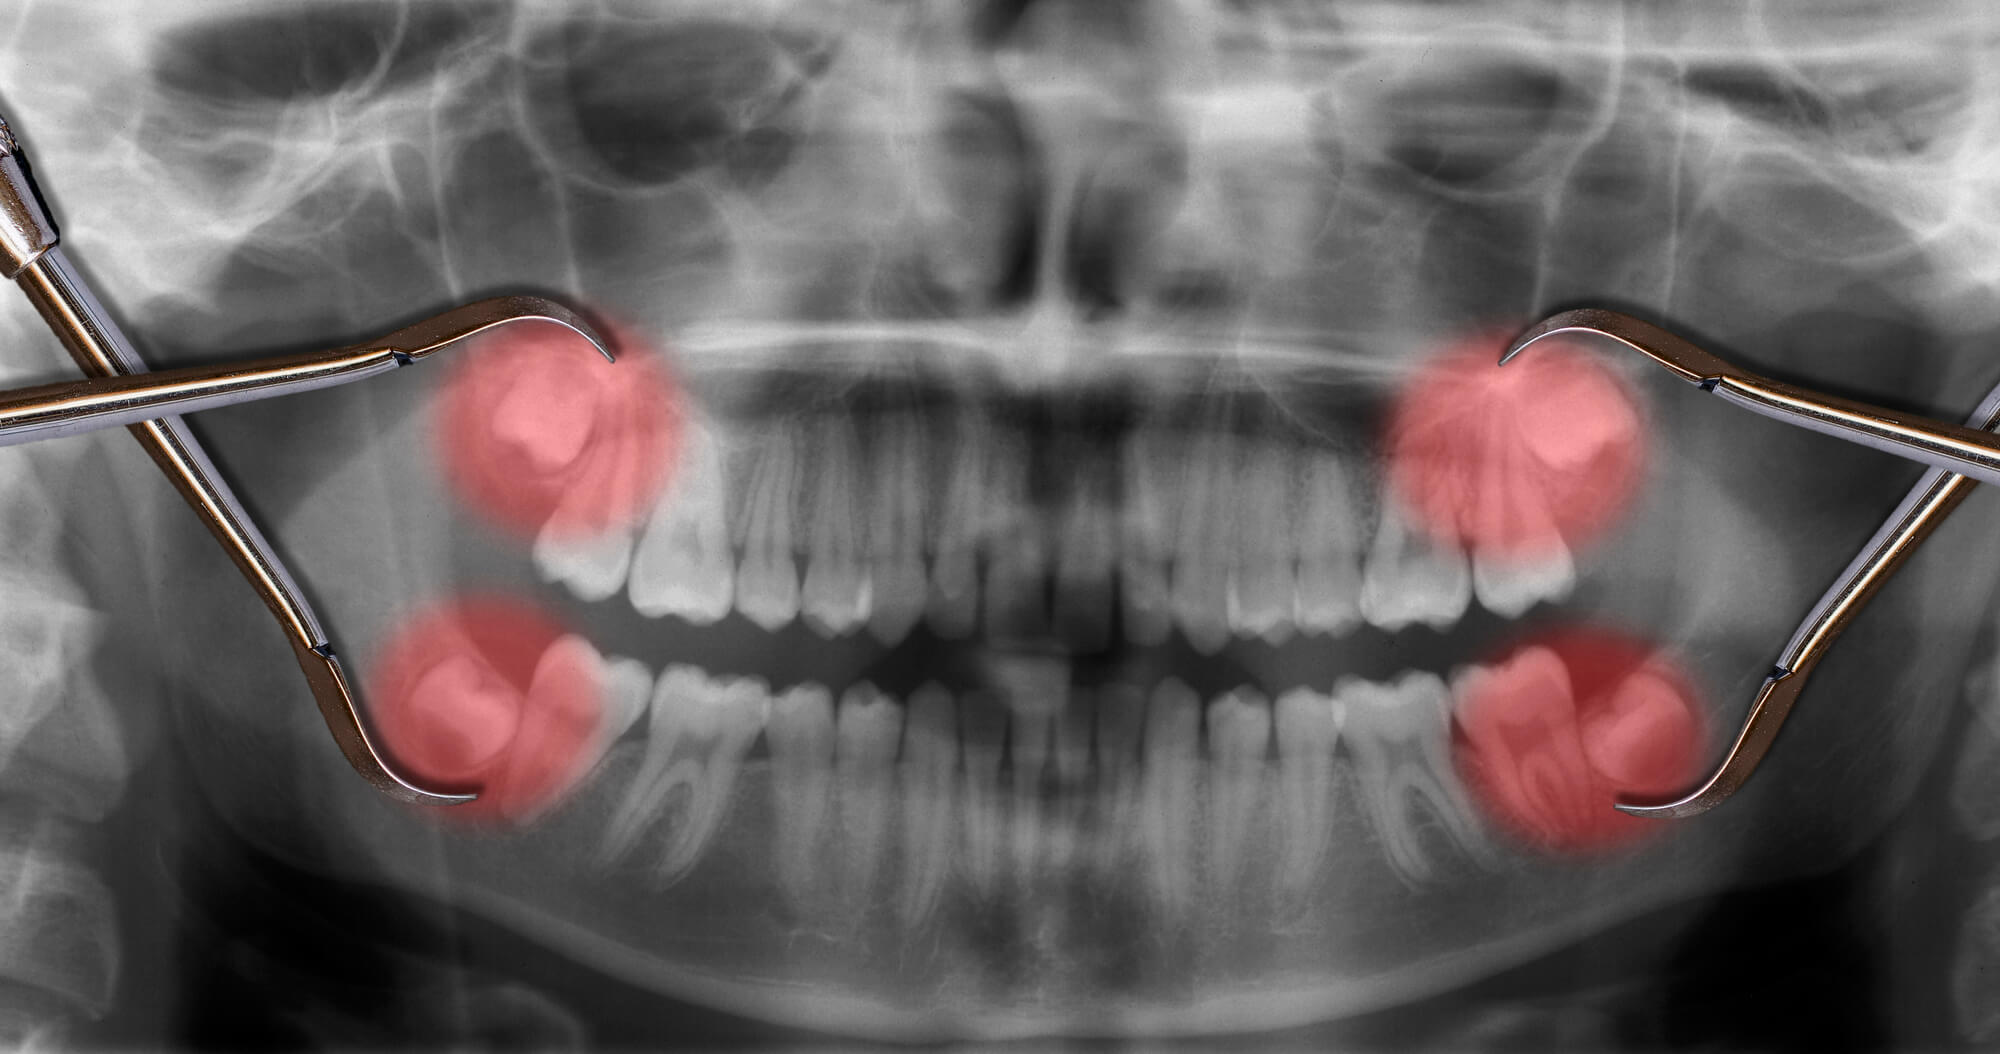

Your wisdom teeth can still be present even if you can not see them all. In some situations, wisdom teeth never erupt or show, but with an X-ray, a dental professional can easily confirm if your kid has them coming.

Wisdom teeth can affect oral health, whether or not they are visible. In fact, impacted teeth that have not broken through the gums can occasionally cause more issues than visible wisdom teeth. Here's what you need to know about wisdom teeth infections, which are the most frequently reported related issues.